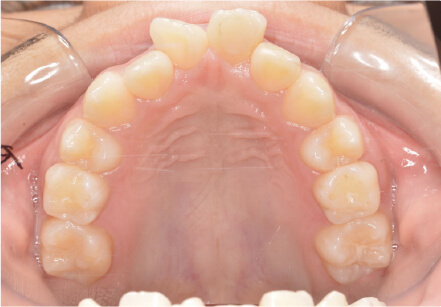

9歳

/

男性

相談内容

下の歯が重なっている。

カウンセリング・診断結果

myoからの移行

治療内容・方法

全額アライナー矯正

術後の経過・現在の様子

上下3〜3fix使用

治療のリスク

痛み・歯根吸収・歯肉退縮・虫歯・後戻り

費用・治療期間

880,000円、1年2ヶ月

トレーニングなど